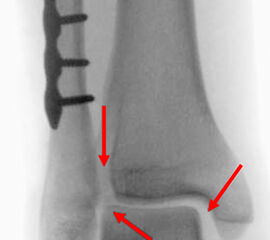

Die Standard-Röntgenaufnahmen des oberen Sprunggelenks bestehen aus drei Aufnahmen: der antero-posterioren Aufnahme (ap), der antero-posterioren Aufnahme mit Innenrotation des Unterschenkels von 20° („Mortise view“), sowie der streng seitlichen Aufnahme (siehe S2-Leitlinie Sprunggelenksfraktur). In der Röntgen-Bildgebung sollte neben den klassischen Frakturzeichen die Integrität der Syndesmose beurteilt werden. Dies erfolgt über die Beurteilung der Breite des lateralen und medialen Gelenkspalts („medial clear space“), des tibiofibularen Abstands 1cm oberhalb des OSG-Gelenkspalts („tibiofibular clear space“), bzw. der tibiofibularen Überlappung. Eine Verbreiterung des tibiofibularen Abstands über 5 mm oder die Erweiterung des medialen Gelenkspalts können Zeichen einer begleitenden Syndesmosenverletzung sein. (Abbildung 3) 6.